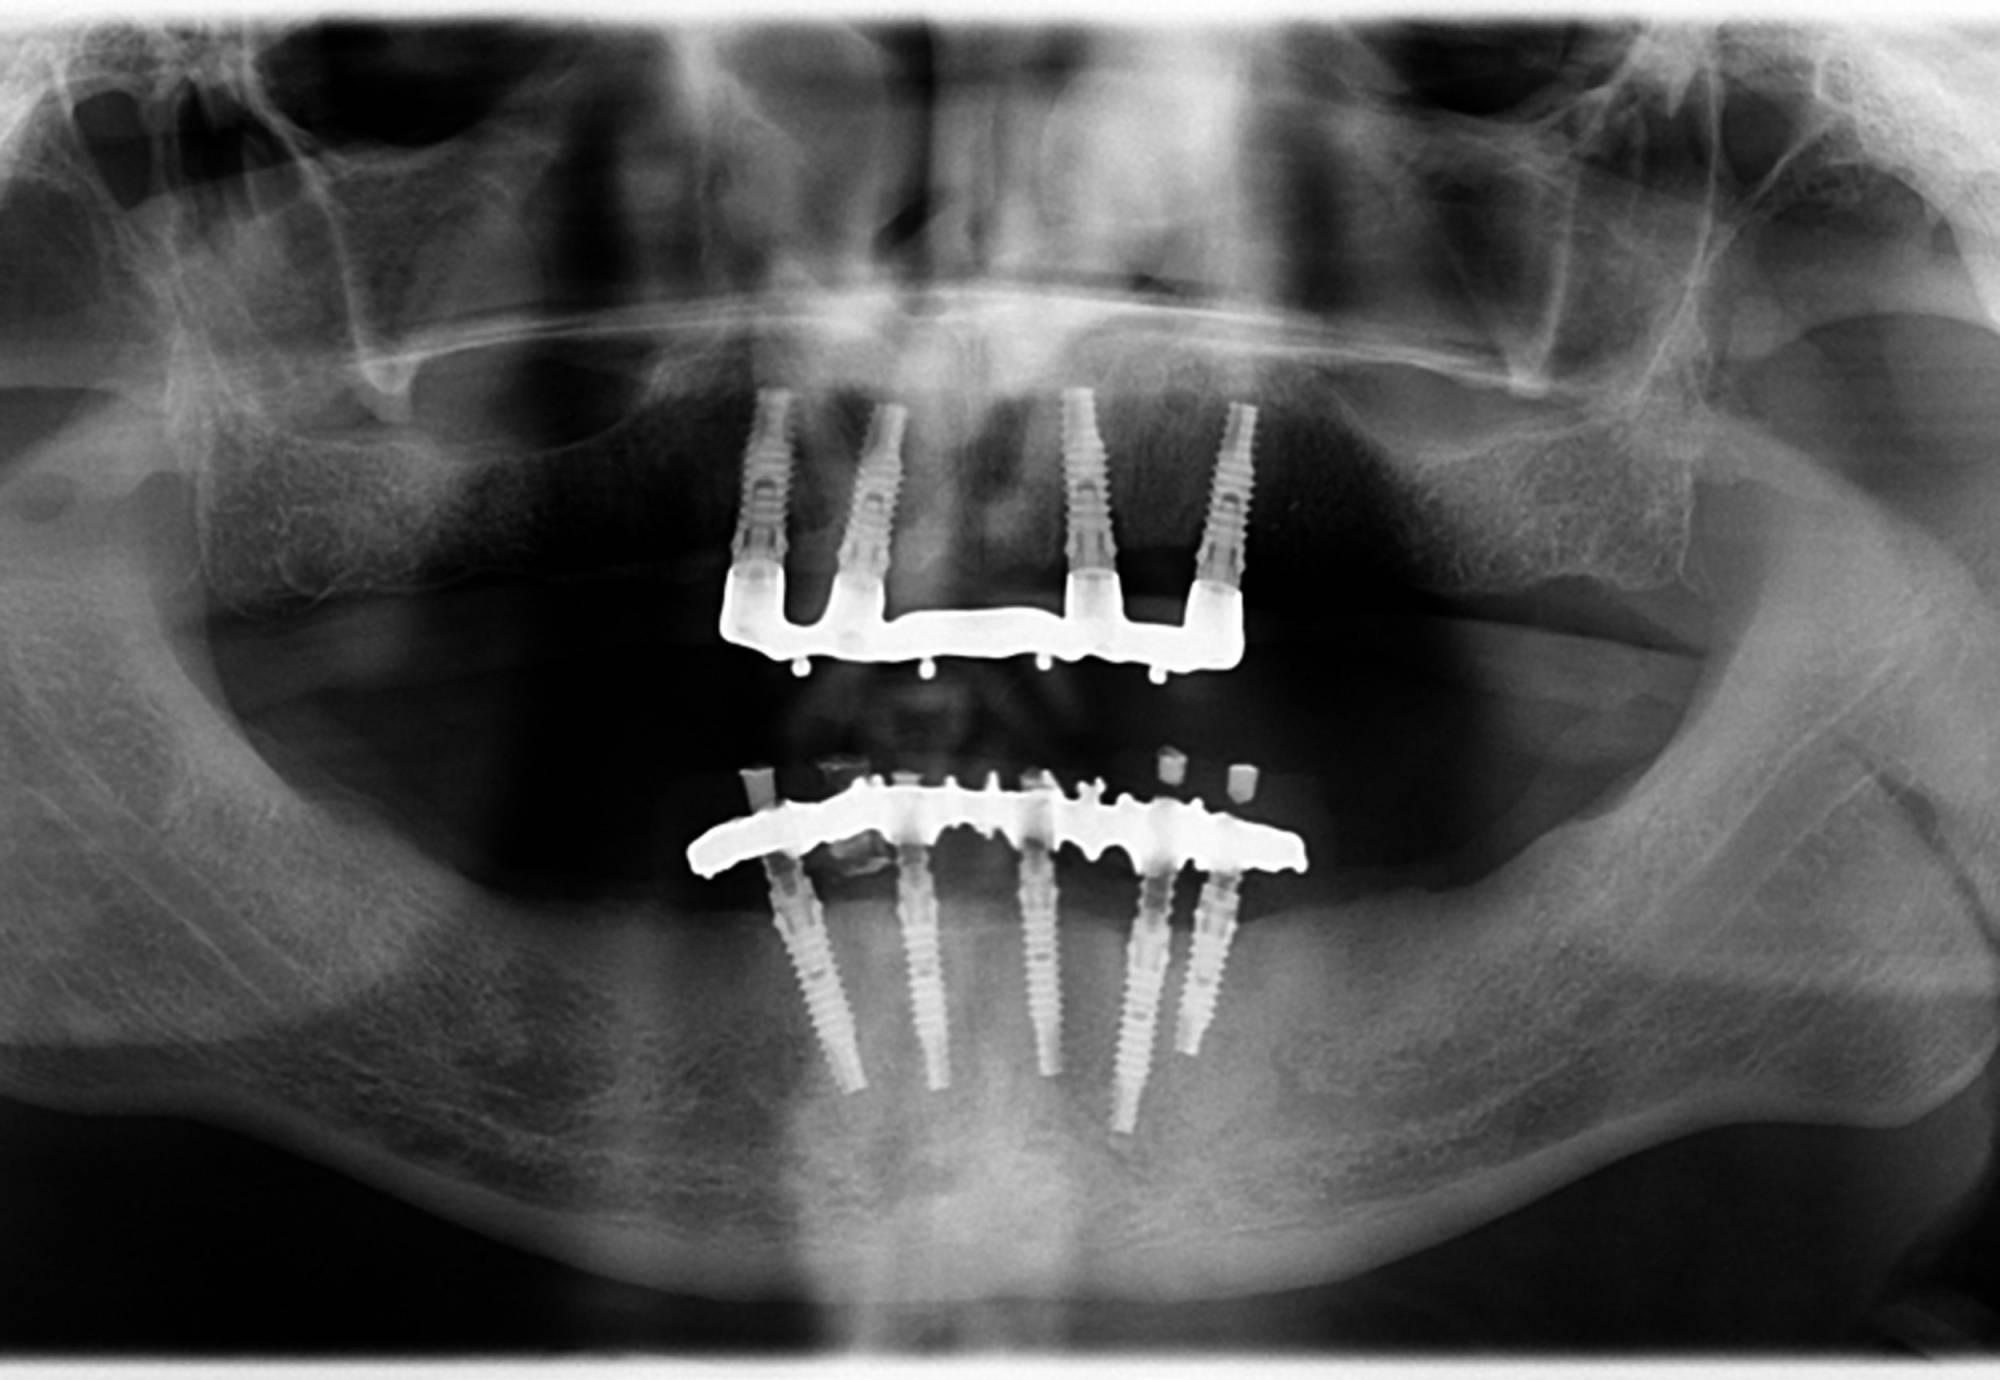

Generalmente devono trascorrere alcuni mesi tra l’intervento chirurgico di inserimento di un impianto e la realizzazione della protesi da fissare ad esso.

In questo lasso di tempo, nel quale l'impianto è sommerso sotto la gengiva e si avvia il processo di guarigione ossea, si realizza l'osteointegrazione, ovvero un intimo contatto fra l’osso e la superficie biocompatibile in titanio dell’impianto.

Tuttavia, in alcuni casi selezionati, è possibile protesizzare gli impianti subito dopo il loro posizionamento, nel giro di pochi giorni o addirittura nel corso della stessa seduta: questa tecnica è definita “carico immediato” e consente al paziente di entrare in Studio con la sua vecchia dentiera e di uscire il giorno stesso con una protesi fissa.

Una tecnica recente e molto apprezzata è l’implantologia computer guidata. L’anatomia della zona da operare è studiata con la Tomografia Computerizzata, simulando al computer, con un software di alta precisione 3D, il posizionamento degli impianti. Sulla base dei dati elaborati dal software si realizza in laboratorio una mascherina chirurgica che guiderà gli strumenti e gli impianti nella corretta posizione nell’osso del paziente, rendendo l’intervento più sicuro e veloce.